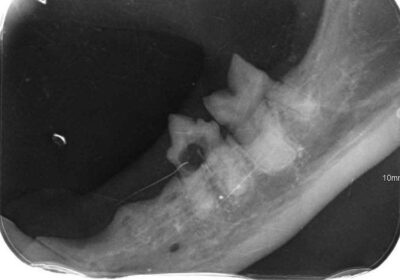

Zaczęło się od trudności z jedzeniem 🍽️, zgłoszonych przez tymczasową mamę, które skłoniły nas do dokładniejszej kontroli. Podczas wizyty weterynaryjnej okazało się, że zęby Loli wymagają pilnej interwencji. Została więc skierowana na zabieg stomatologiczny 🦷, w trakcie którego wykonano RTG jamy ustnej. Badanie wykazało sporo zmian – aż 8 zębów musiało zostać usuniętych.